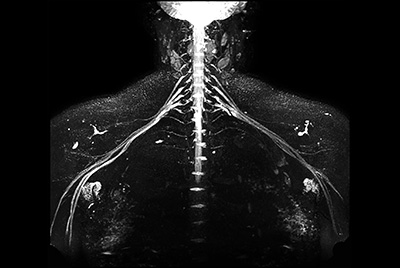

Brachial plexus tumor

Brachial Plexus with a hemangioma

Brachial Plexus lesion